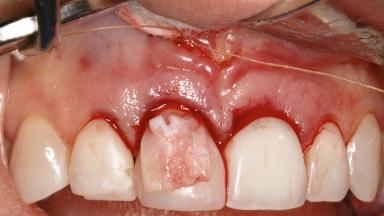

Late Presentation of Peri-Implant Mucositis Requiring Soft-Tissue Augmentation and Esthetic Crown Lengthening at Implant Site 11

Biological or technical complications around implant-supported prostheses place a significant burden on patients as well as the surgical and restorative team. Inflammation of the peri-implant soft tissues is often the first sign that something has gone awry. While there is never a good time for a complication, late presentation of inflammation in the soft tissues around a long-standing prosthesis triggers a period of research and review of the case in order to ascertain the treatment history and its possible contribution to the etiology of the situation. This becomes more complicated in situations where a patient has not received regular maintenance and clinical/radiographical examinations due to personal, financial, or professional reasons. When the complication occurs in the esthetic zone, the complexity of the situation expands exponentially, as the only acceptable outcome in the patient’s eyes will be the maintenance of the esthetics of the prosthesis.